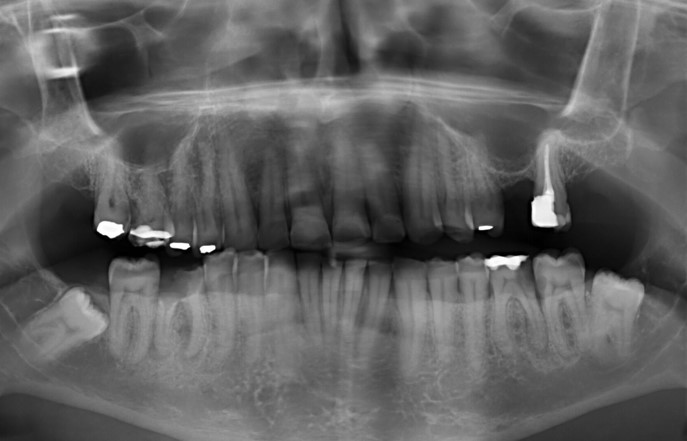

Ik zat te kijken naar de foto en zag niets geen wortel kanaal ontsteking .Zoals de kaakchirurg aan de weledelgeleerde tandarts schreef in zijn mail

Toen zei iemand in het langs gaan een kleine onsteking wees op dit stukje

Kijk ook goed op andere fotos een kleine ontsteking . (zie pagina fotos)

Ik weet nu dat het maar een tandvlees onsteking was . Deze had de wortel niet aangetast .

Dit was de foto die de tandarts padrao op 07-10-2021 ter beschiking had

Er is geen nieuwe foto tenminste geen begin foto gemaakt Element 36 is niet meer te behouden Deze foto is pas gemaakt nadat hij element 36 had weg gefreest en 37 was al geopend voor een wortel kanaal behandeling

Er zijn op de fotos ookop element 36 en 37 geen wortepunt onstekingen te zien